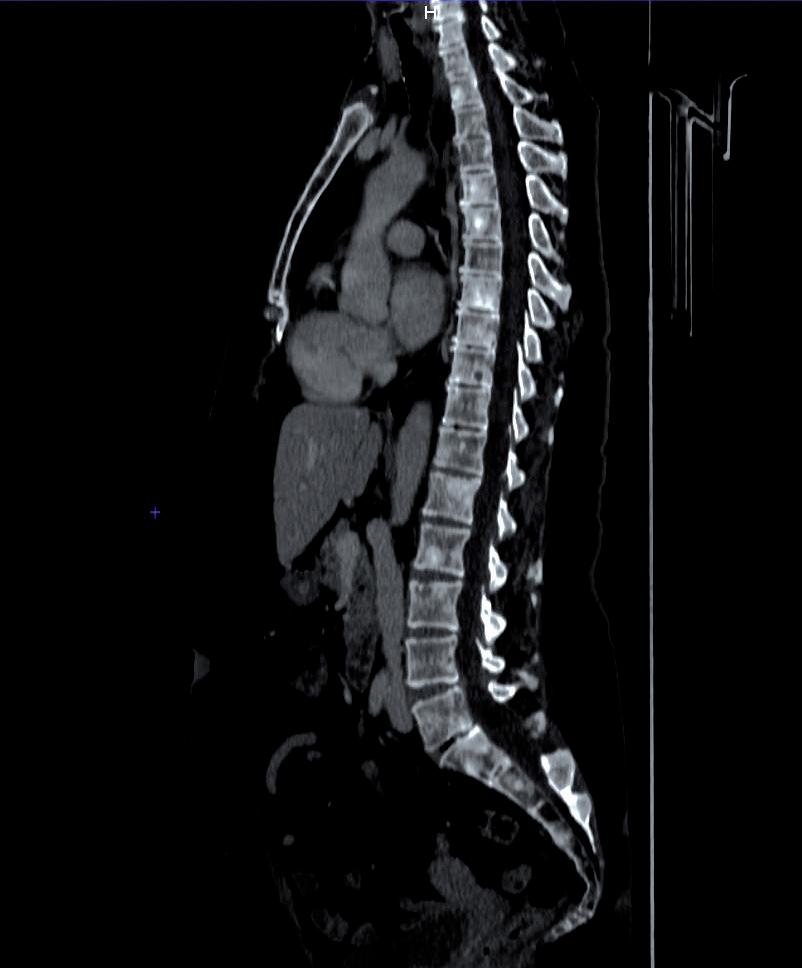

In considerazione della sintomatologia riferita dalla paziente con sensazione di rigidità nucale, difficoltà ai movimenti, dolore base collo, instabilità nella marcia,

parestesie arti inferiori e ipostenia estremità distali esacerbate dal movimento, previa valutazione Multidisciplinare, si completava con RM encefalo + rachide mdc in data 18/07/2023. L’esame confermava la progressione a livello cerebellare destro con comparsa di multiple nodulazioni leptomeningee di natura ripetitiva a livello di tronco encefalico, nervi cranici, superficie midollo spinale, radici cauda e sacco durale (figure 1-3).

Figure 1, 2 e 3. RM encefalo-tronco encefalico-rachide MDC basale pre-trattamento con T-DXd.